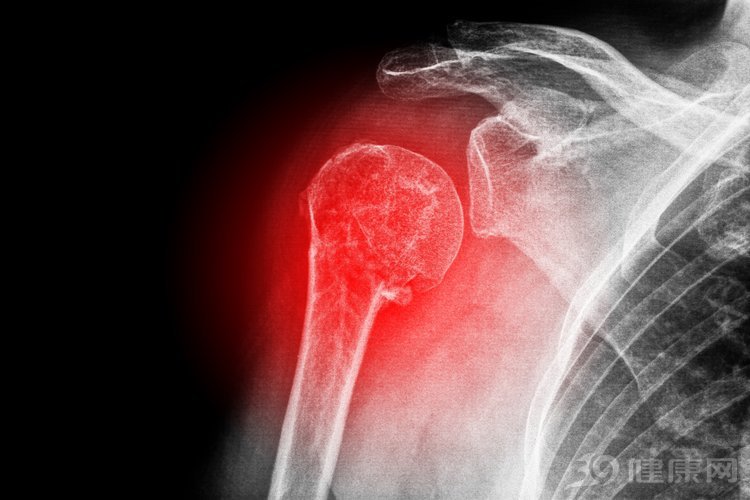

一、关节疼痛

关节出现疼痛会是骨性关节炎的典型症状,多表现为上下楼梯膝盖疼痛,这也是病情后期会出现功能障碍的原因。关节疼痛严重的情况下,会对睡眠质量造成影响,对痛楚比较敏感的妈妈们,有可能会出现夜半疼醒的情况,甚至会导致失眠。